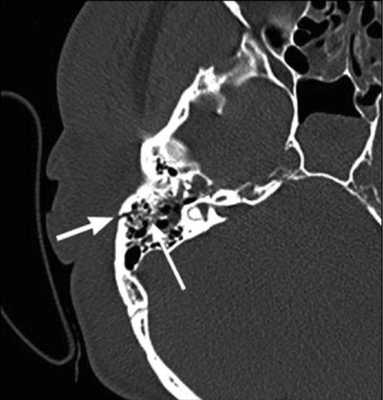

Преимущества КТ височных костей

Компьютерная томография является оптимальным вариантом для исследования костей, в том числе черепа. Костная ткань хорошо поглощает рентгеновские лучи, в результате получают четкие ее изображения. Данный метод незаменим в диагностике скрытых переломов и трещин, он хорошо выявляет деструктивные изменения.

На КТ-снимке виден перелом пирамиды височной кости (указан стрелками)

Другими преимуществами мультиспиральной томографии являются:

высокая скорость сканирования;

относительно низкий уровень лучевой нагрузки;

неинвазивность и безболезненность;

доступность для выполнения пациентам с ферромагнитными имплантатами, электронными устройствами;

возможность получения трехмерной модели исследуемой зоны.